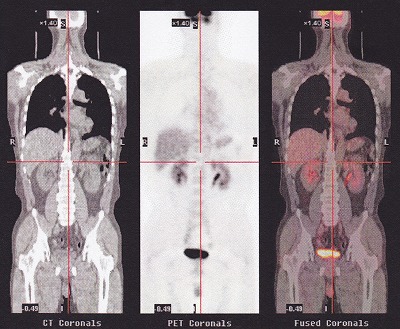

11.19.17:26 腫瘍ドック |

PET-CT検査と呼ばれているものです。

陽電子放射断層撮影装置のことで、ポジトロン・エミッション・トモグラフィー[PositronEmissionTomography]の略語です。X線CTのような形をした「カメラ」を用いて全身や心臓、脳などにおいて、病気の原因や病巣、病状を的確に診断する新しい検査法です。

がん細胞を見つけるものなのですが、発想がおもしろい。

細胞は、ブドウ糖を必要としているので、検査前にブドウ糖を摂取せずに検査に望みます。悪性の細胞は、良性の細胞の細胞と比べて3倍から8倍ブドウ糖を吸収し、急激に大きくなるらしい。

そこを利用して、「擬似えさ」を作る。。これが、凄いですね。

限りなく、ブドウ糖なのですが、構造の一部に放射性物質を組み込む。

18F-FDG

グルコース(ブドウ糖)に目印となる「ポジトロン核種(=陽電子放出核種)」を合成した薬剤です。

正式名称はフルオロデオキシグルコースといい、性質はブドウ糖とほぼ同じです。

この擬似えさを、注射で体内へ投入すると、すべての細胞がこの餌を取り込もうとする。悪性のがん細胞は、大食いなのでたくさん食べるという仕組み。

だけど、ブドウ糖だと思って取り込んではみたものの、やっぱり偽者なので吸収できない。

結局は、尿となって流れでしまう。。ということらしい。

この、細胞が取り込んでいる隙に、撮影すると、おおく取り込んでいる部分が赤く光る!この検査は、がん細胞が、自分から光ってくれる。。

ただし、尿となって流れ出すので、肝臓、腎臓、そして終着点の膀胱は真っ赤に光る。

口周りや、脳も活発に活動しているので、多く取り込み光る。

真っ黒な肺の下に、薄く光っているでっかいものが、肝臓、大きいものですね。。その下に二つある光っているのが、腎臓、股間で光っているのは、膀胱ですね。。その下が光っているのは?なぜなんだろう?(笑)

ということで、まったく問題ございませんでした。

「何も無いものは、何も無いとしか言いようがない!」と先生に言っていただけました。

が、急性腹痛による、腸閉塞については、、、原因不明のまま、、、ストレスなどによる一次的な痙攣。。。

大丈夫! って思い込むことが大切ですね。